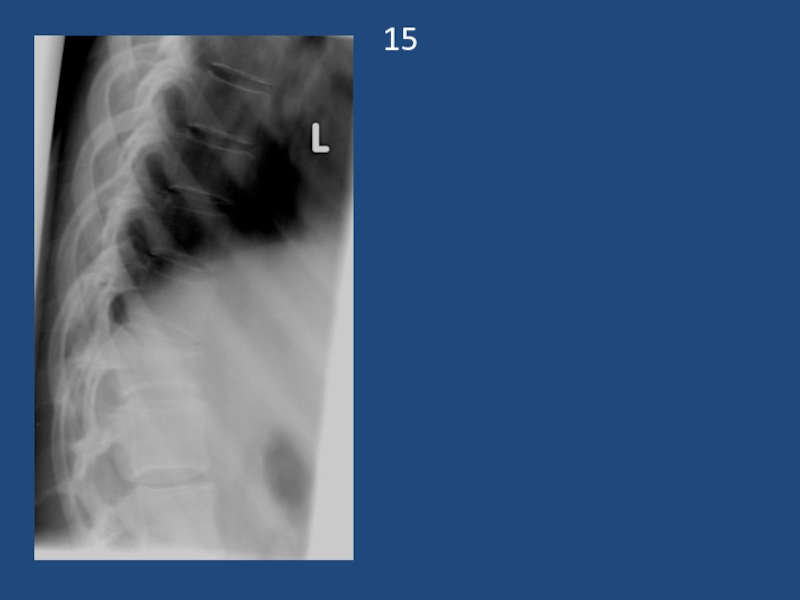

Множественный перелом 5,6,7 ребер справа,со смещением отломков, осложненный тотальный пневмотораксом

2Множественный перелом 5,6,7 ребер справа,со смещением отломков, осложненный тотальный пневмотораксом